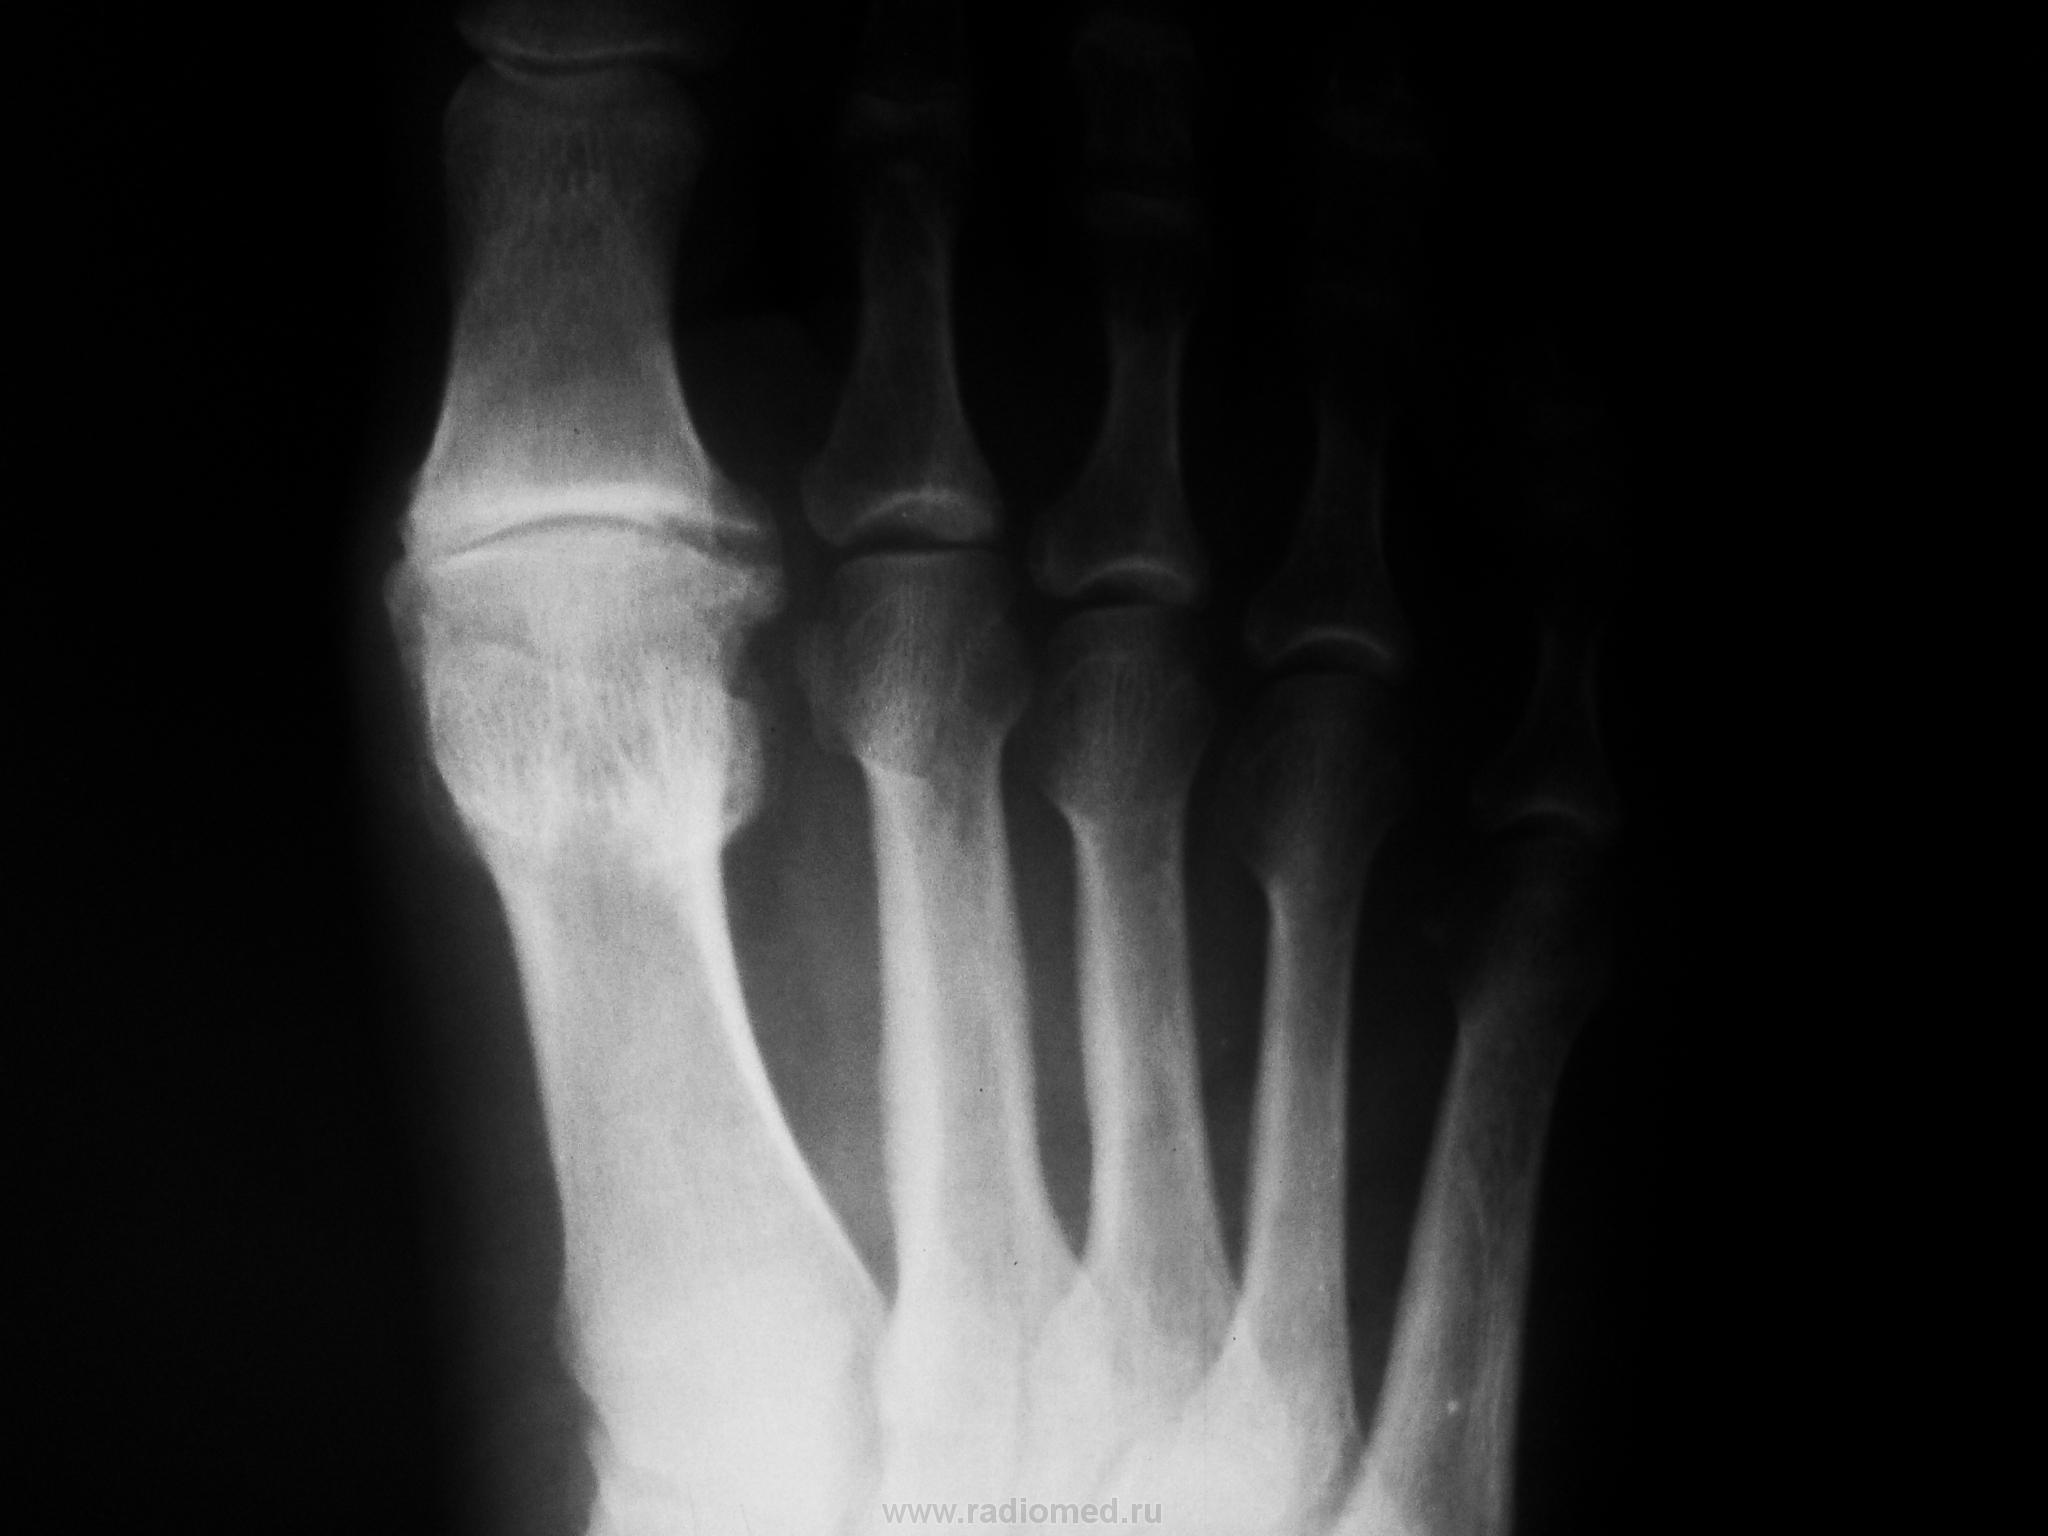

Уважаемая Медея(вот красивое имя у Вас), к сожалению с протезированием данного сустава я не сталкивался, скажите Вы выставили первичный снимок до операции ( вальгус там не большой), какие причины сподвигли докторов заменить сустав? боль? нарушение опоры, ходьбы?у Вас это рядовая операция или "будем пробовать" , с таким варусом сложно обувь подобрать, поперечный свод стопы стал еще шире.....